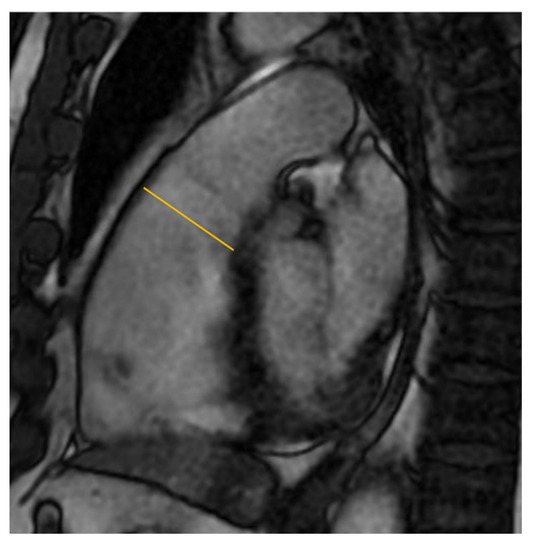

3.5. Tissue Carachterization

3.1. Right Ventricular Dilatation

3.2. Ejection Fraction